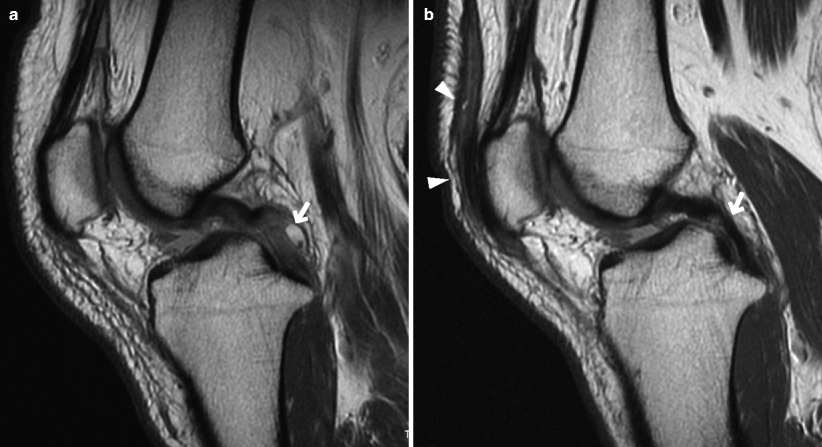

Gross anatomy the pcl attaches to the posterior intercondylar area and passes anterosuperiorly to insert into the lateral surface of the.